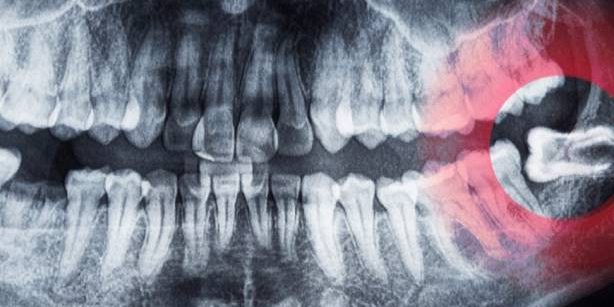

Imaging

-

Radiografia endorale: per carie, infezioni periapicali

Ortopantomografia: per posizione e inclusione

CBCT (nei casi complessi): per valutare rapporti con il nervo alveolare inferiore